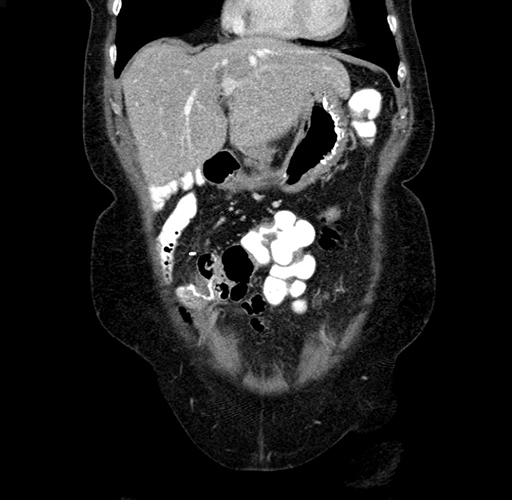

Pre-Chemo: Axial Venous

Axial Venous